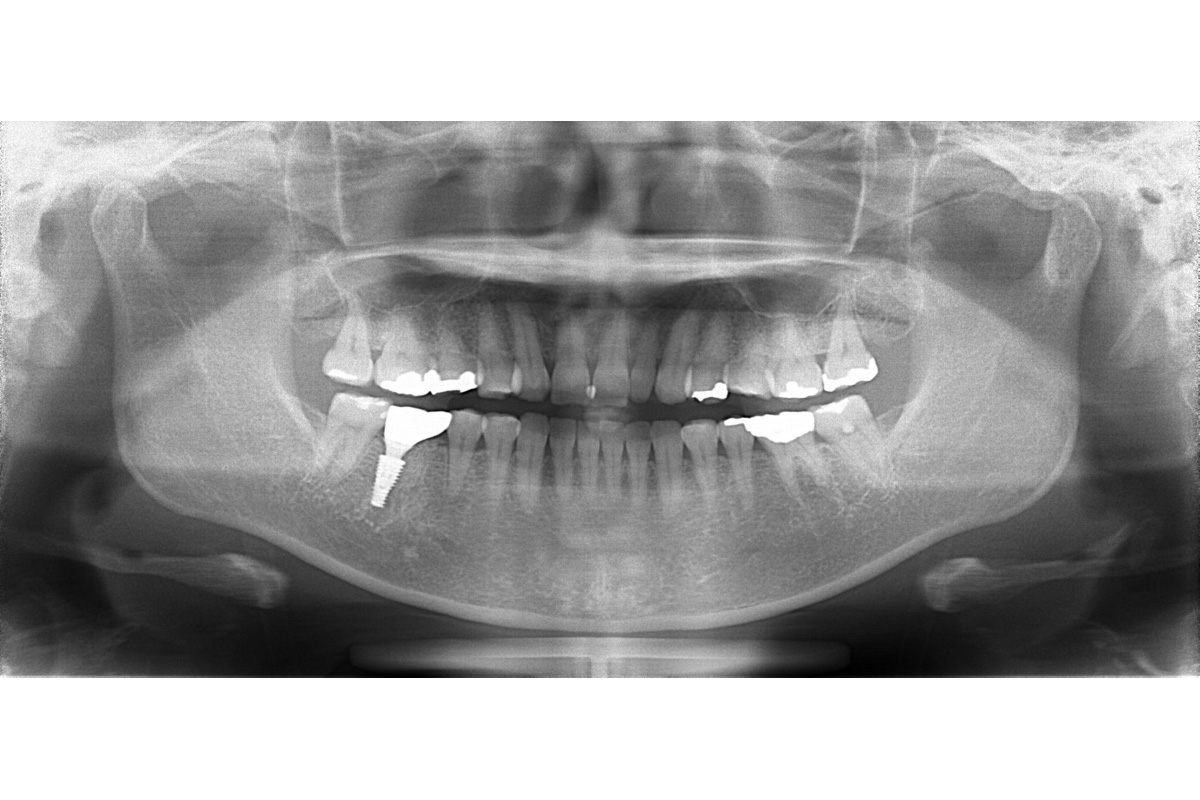

治療後